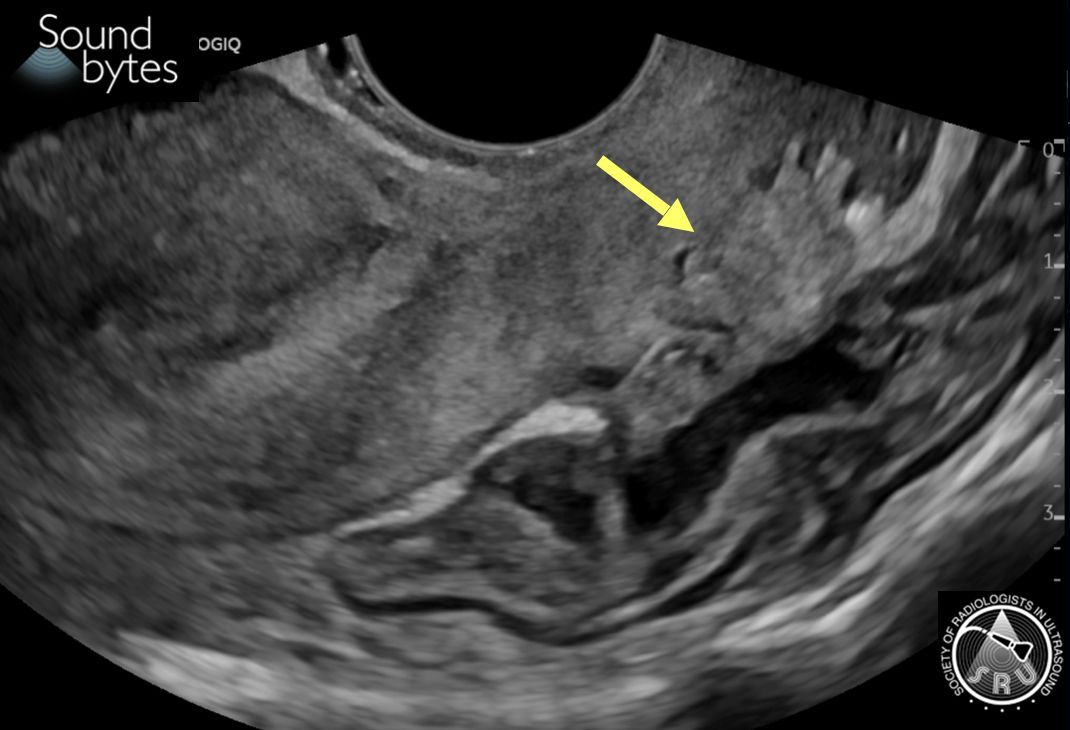

71 yo man with persistent right scrotal pain and swelling. What is your sound diagnosis?

Case courtesy of Drs. Boyan Fan and Marta Flory, Stanford University

Dx: (Fat containing) *Indirect* Inguinal Hernia

Findings: Herniation of intraabdominal fat between the inferior epigastric and the external iliac vessels.